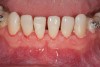

Fig 11. Interim orthodontic phase and transitional bonding to be accomplished based on Bolton analysis now that overly sufficient space has been appropriated for the creation of proportionately correct mandibular incisors. Once transitional bonding is complete, orthodontic finishing will be performed and any remaining spaces closed.

Figure 11